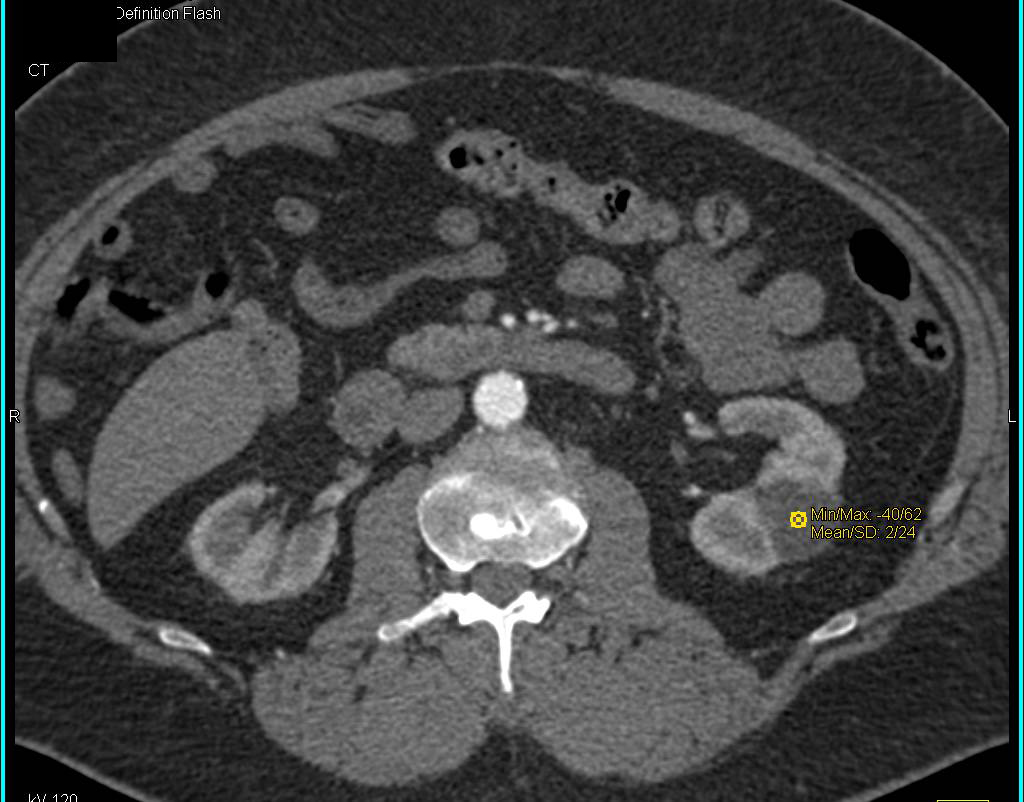

Duplicated Lower Pole Collecting System on the Left with Dilated Left Ureter and Aberrant Insertion into the Bladder